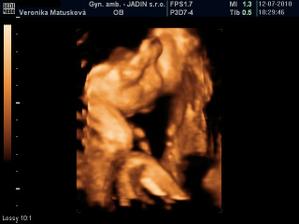

Adamko - 3D/4D

No tot vidno, že je náš syn, sa hanbil a hanbil až sa ukazovať nechcel....ale niekedy sa to podarilo, aj ked to nie je nejaká sláva. Pán doktor nám potvrdil chlapčeka, tak sme radi, vajká ukazoval ako len vedel len toho pipíka stále schovával. Ale je to za nami, pán doktor nás pekne popísal čo je kde, poodmeral nás a povedal, že je všetko v poriadku.